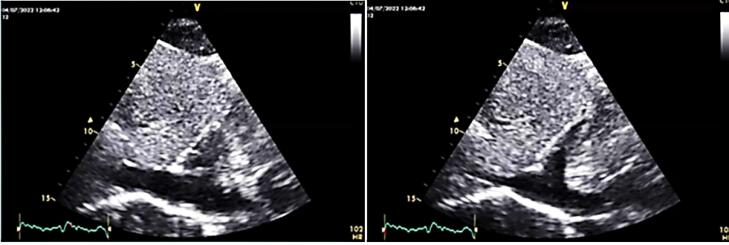

我们知道,心脏黏液瘤是最主要的心脏肿块之一,但这种类型的肿瘤的实验室结果是非特异性的,诊断是通过影像学。在这个病例中,我们报告了一名61岁的男子,他最近出现呼吸困难的病史,实验室检查显示红细胞增多症伴血小板减少症。腹部超声、骨髓穿刺及活检未见明显诊断,但超声心动图发现右心房有大肿块。在心脏病专家和心脏外科医生会诊后,计划进行手术切除,之后血小板减少症得到解决。在这个病例报告中,我们想写心脏黏液瘤和血小板减少症之间罕见的相关性,并表明早期诊断和治疗这种疾病可以帮助和完全治愈患者的抱怨。

As we know, cardiac myxoma is one of the most primary cardiac masses but laboratory findings in this type of tumor is non-specific and the diagnosis is by imaging. In this case we have reported a 61 year old man came to the emergency ward of hospital with history of recent onset dyspnea and The Laboratory finding indicates polycythemia with thrombocytopenia. Ultrasonography of abdomen and bone marrow aspiration and biopsy revealed no significant diagnosis but on echocardiography a large sized mass was detected in right atrium. After cardiologist and cardiac surgeon consultation the plan was to surgical Excision and after that the thrombocytopenia has been resolved. In this case report we want to write about a rare correlation between cardiac myxoma and thrombocytopenia and show that early diagnosis and treatment of the disease can help and totally cure complaints of patient.